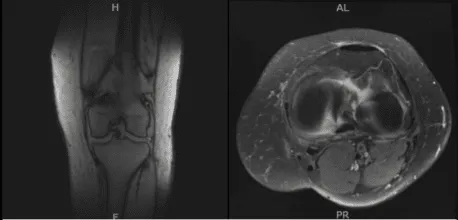

An MRI was done for diagnosis. There is a moderate-sized joint effusion and capsular inflammation. The anterior and posterior cruciate ligaments are intact. There is a complex tear of the body and posterior horn of the medial meniscus. The lateral meniscus is intact.

The quadriceps tendon and patellar tendon are intact. The medial and lateral collateral ligaments are intact. There is moderate patellofemoral chondromalacia with 15 mm partial-thickness erosion involving the medial facet of the patella. No subchondral defect or fracture identified. There is a 10 mm enchondroma in the distal metaphysis of the femur medially.

No osteochondral defect or fracture identified. On the result of the MRI, there was a complex tear of the body and posterior horn of the medial meniscus. Moderate patellofemoral chondromalacia associated with moderate-sized joint effusion and capsular inflammation.

MRI-3T Left Knee Non-contrast